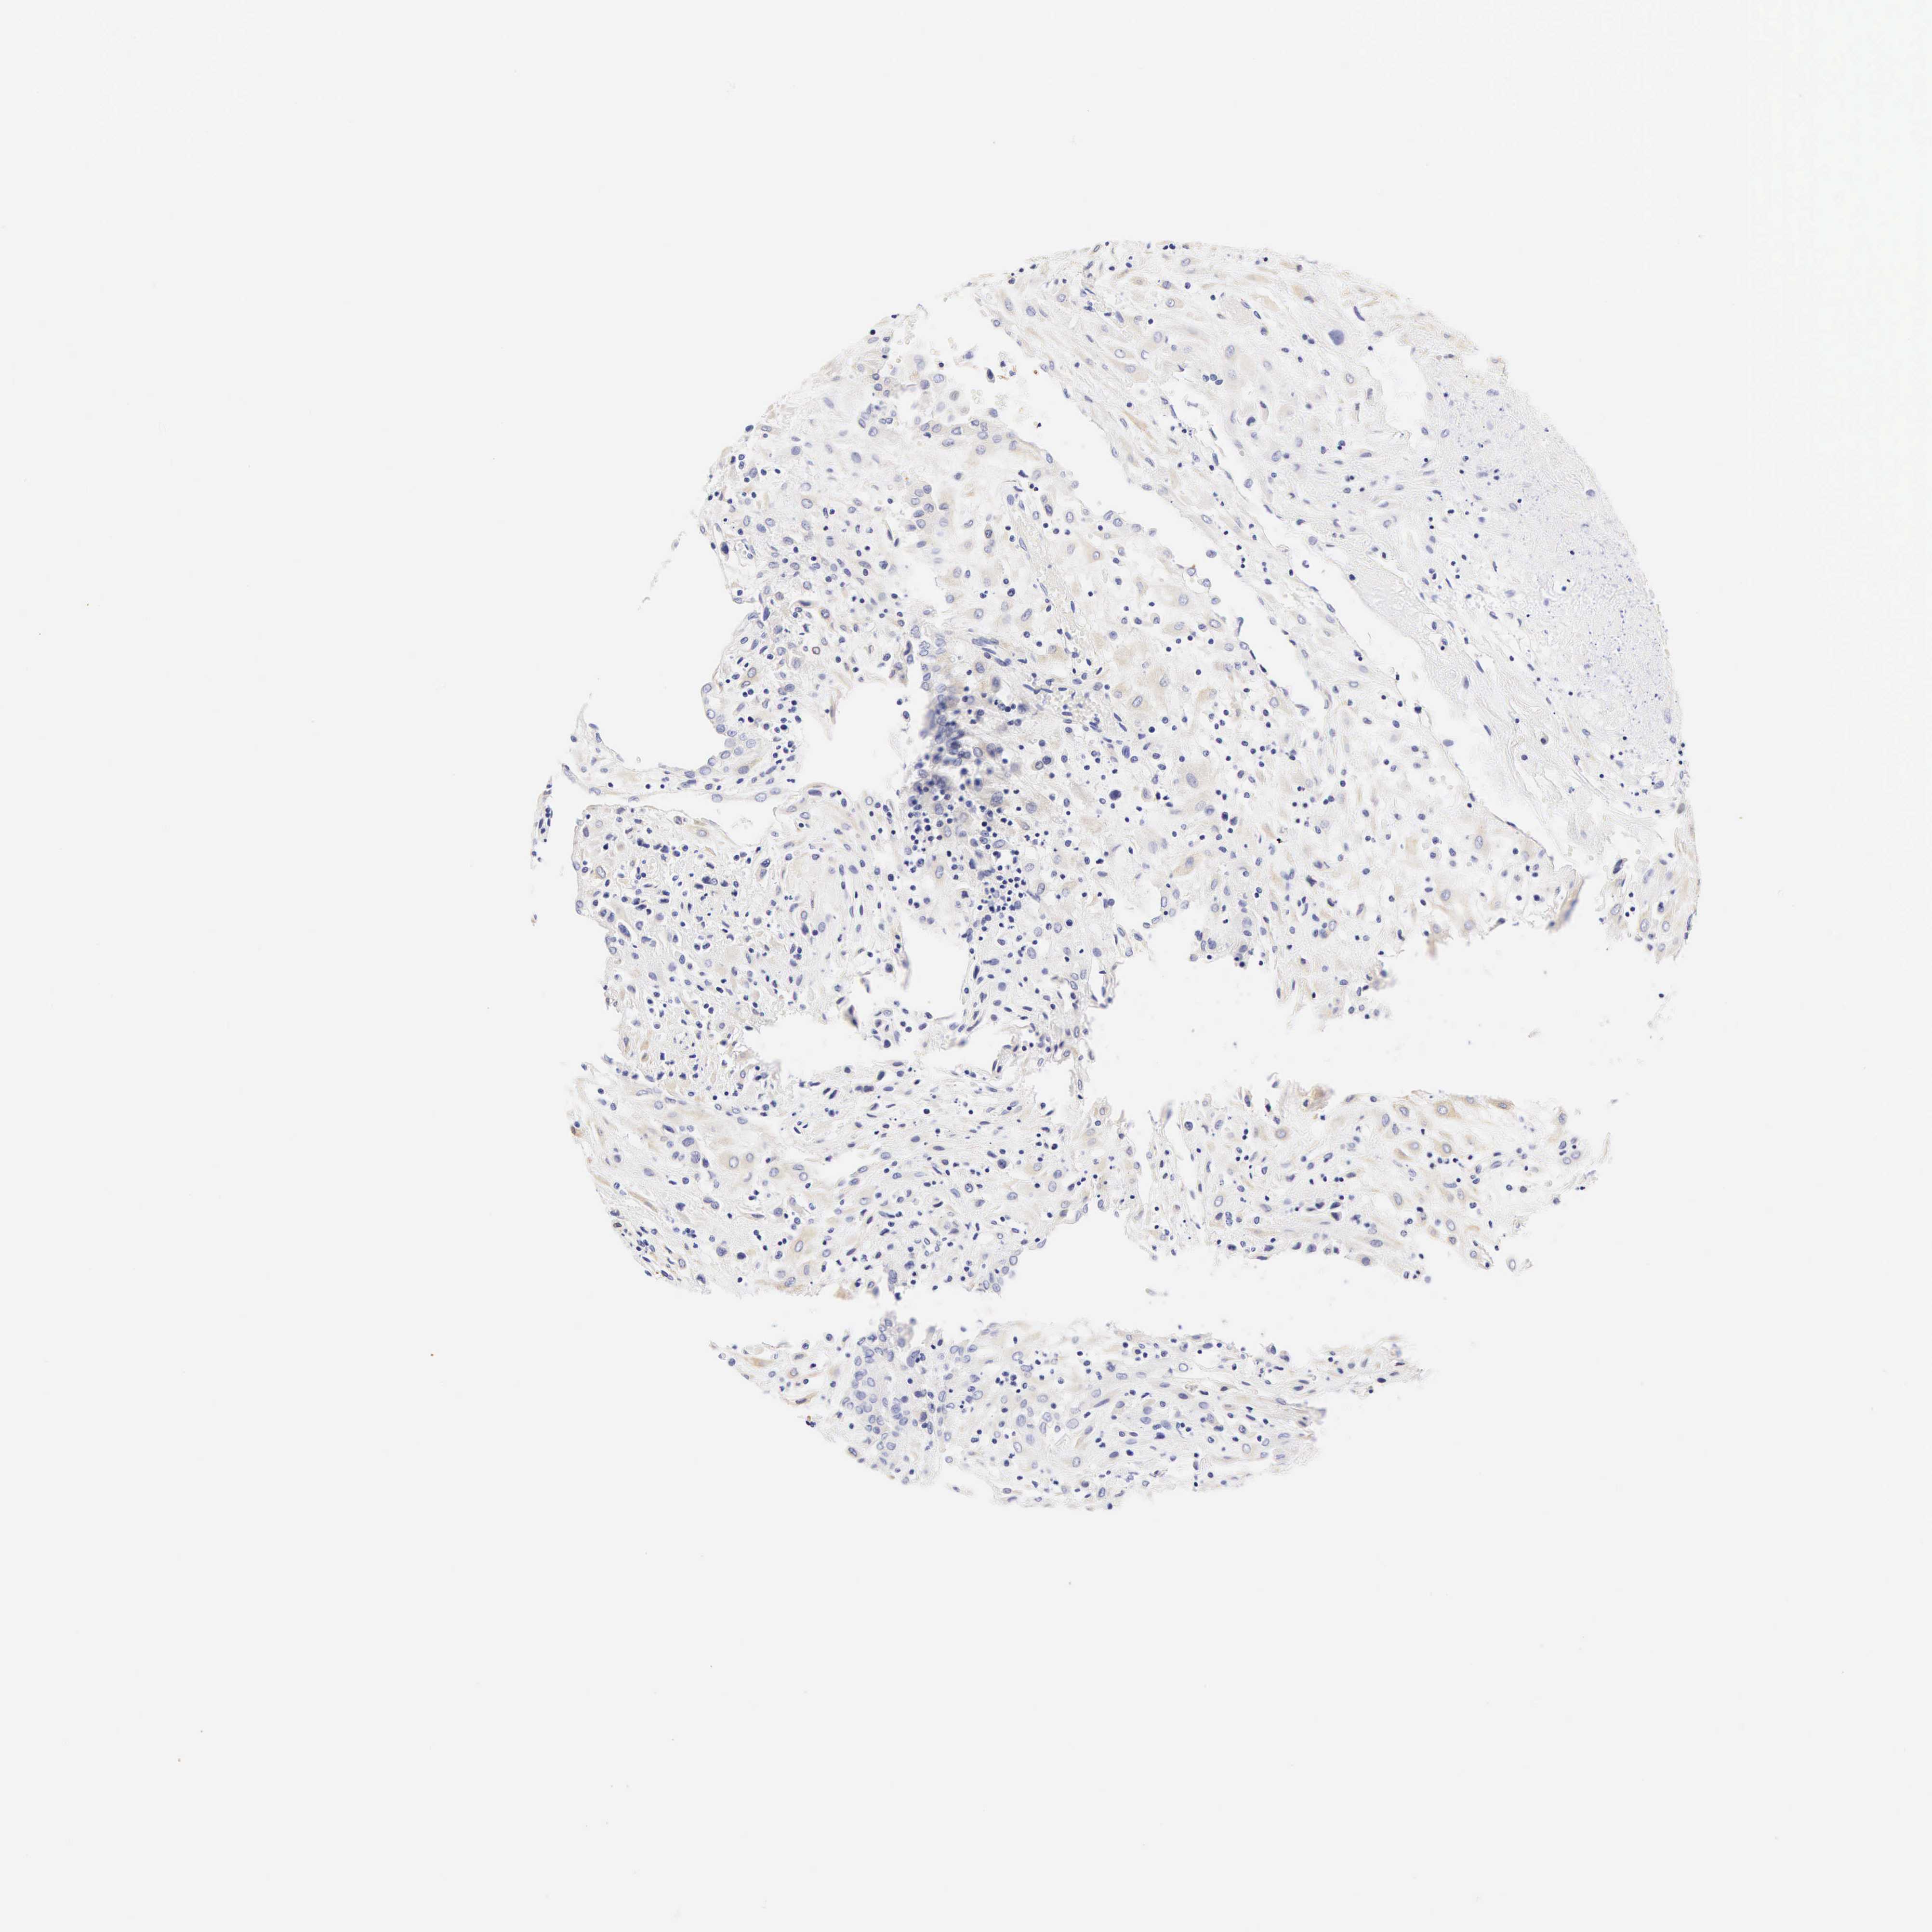

PLACENTA - Antibody stainingi

Antibody staining in the annotated cell types in the current human tissue is reported as not detected, low, medium, or high, based on conventional immunohistochemistry profiling in selected tissues. This score is based on the combination of the staining intensity and fraction of stained cells.

Each image is clickable and will lead to virtual microscopy that enables deeper exploration of all samples and also displays staining intensity scores, fraction scores and subcellular localization as well as patient and tissue information for each sample.

Antibody HPA014263Antibody CAB000007

Decidual cells Not detectedNot detected

Trophoblastic cells Not detected-